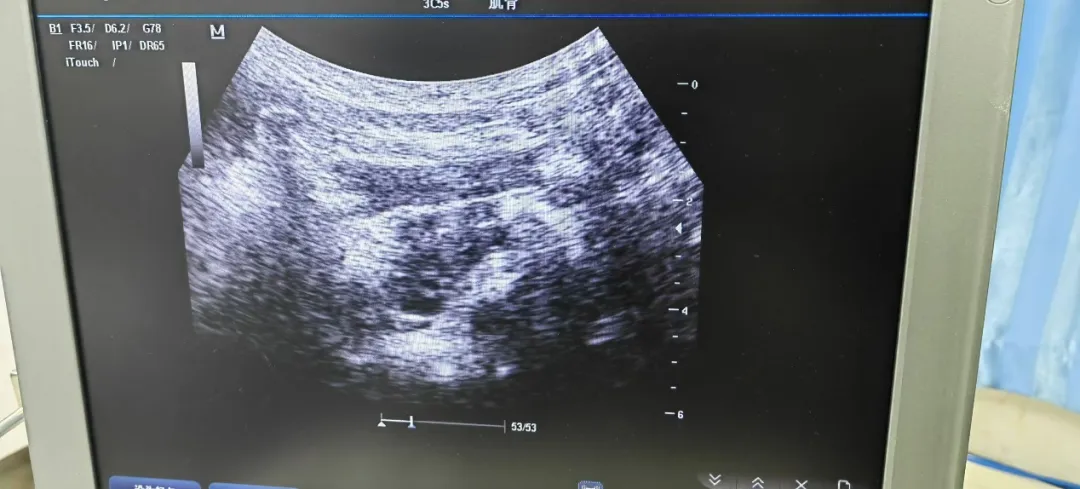

患者,男,76岁,诊断“带状疱疹后神经痛、神经病理性疼痛”,主要疼痛部位为右侧颈肩部,病程3年,视觉模拟(VAS)评分7分,曾行神经阻滞治疗及脊髓电刺激(临时)治疗,效果均欠佳,严重影响患者情绪及日常生活。本次入院行“超声引导下C3、C4神经根后支射频热凝术、C4神经根脉冲射频治疗、颈浅丛射频治疗”,患者术后疼痛明显缓解,VAS评分3分。